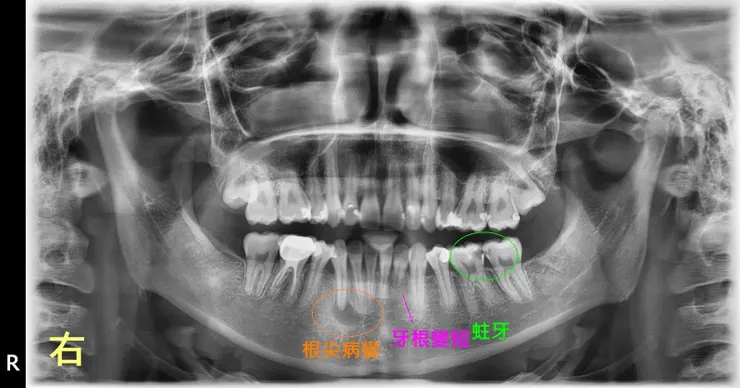

接下來是比較精采,喔,不,警世的例子,說明為何我要幫每一個新病人照x光片。

有些硬組織的病變,例如蛀牙、根尖病變,是臨床上不一定肉眼可見的,很容易被忽視,那請問在定檢什麼呢?說起來是從來沒被好好對待過。